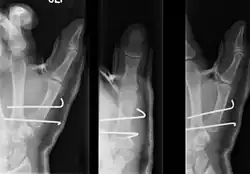

- In the most minor cases of Bennett fracture, there may be only small avulsion fractures, relatively little joint instability, and minimal subluxation of the CMC joint (less than 1 mm). In such cases, closed reduction followed by immobilization in a thumb spica cast and serial radiography may be all that is required for effective treatment.[5]

- For Bennett fractures where there is between 1 mm and 3 mm of displacement at the trapeziometacarpal joint, closed reduction and percutaneous pin fixation (CRPP) with Kirschner wires is often sufficient to ensure a satisfactory functional outcome. The wires are not employed to connect the two fracture fragments together, but rather to secure the first or second metacarpal to the trapezium.

- For Bennett fractures where there is more than 3 mm of displacement at the trapeziometacarpal joint, open reduction and internal fixation (ORIF) is typically recommended.

Regardless of which approach is employed (nonsurgical, CRPP, or ORIF), immobilization in a cast or thumb spica splint is required for four to six weeks.